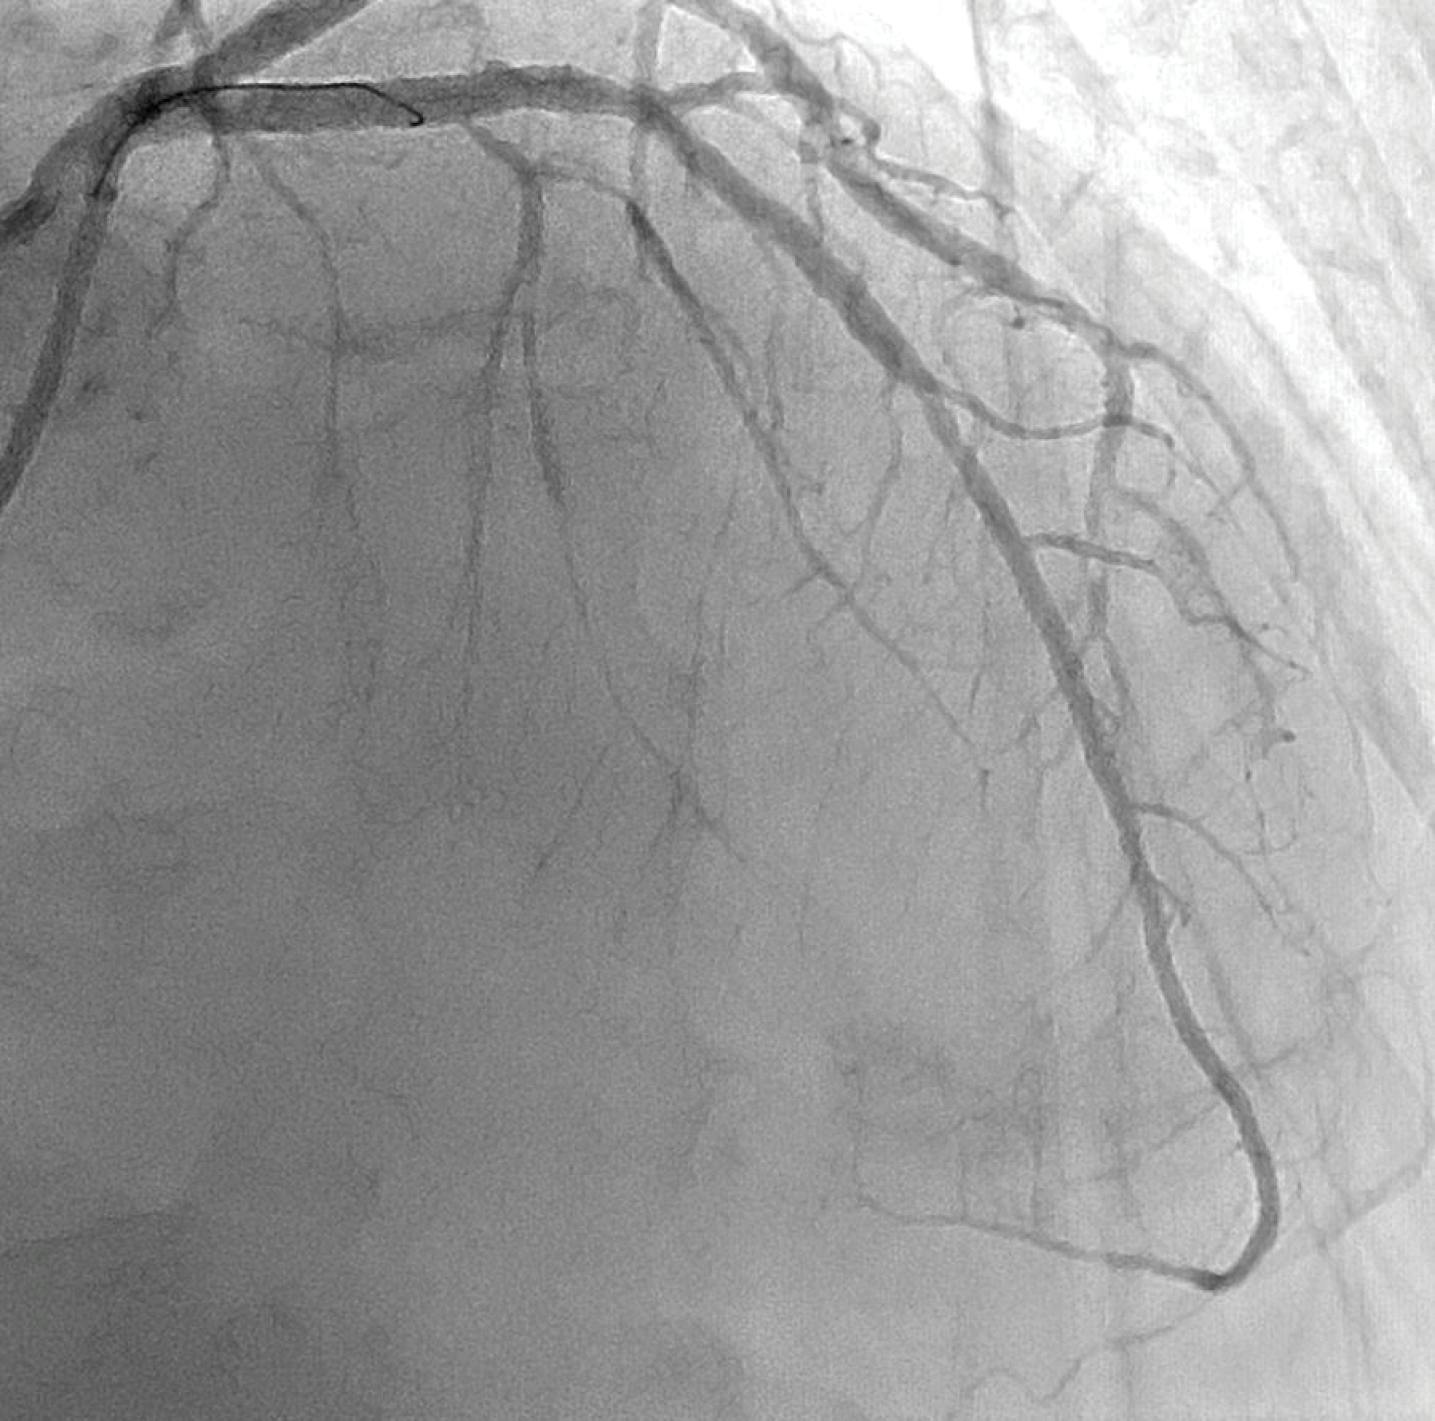

After administration of a loading dose of ticagrelor (180 mg), the occlusion site was successfully crossed with a workhorse guidewire. Sustained mechanical thrombectomy was performed using the Indigo CAT RX aspiration system (Figure 2). The main advantages of this innovative technology in the life-threatening setting of STEMI are the simplicity of setup and ease of use, which allows rapid removal of thrombus and identification of the underlying culprit lesion, thereby facilitating PCI and restoring the epicardial anterograde flow with minimal blood loss. In addition, the 5.3-F Indigo CAT RX catheter is a 6-F–compatible device that navigates easily through tortuous anatomies and allows easy access to distal coronary vessels. After one pass, the intracoronary thrombus was successfully removed (Figure 3) uncovering an underlying significant proximal and mid LAD stenosis (Figure 4). The lesion was subsequently predilated using noncompliant and cutting balloons, followed by a hybrid PCI approach using a newer-generation drug-eluting stent in the proximal LAD and a sirolimus-coated balloon in the mid-LAD.

Figure 2. Coronary angiogram showing the advancement of the Indigo CAT RX aspiration catheter in the proximal LAD.

Figure 3. Coronary angiogram after sustained mechanical thrombectomy with the Indigo CAT RX aspiration system (one pass) uncovering an underlying significant proximal and mid LAD stenosis.

Figure 4. Coronary angiogram after PCI to proximal and mid LAD showing a good final angiographic result with normal epicardial and microvascular coronary flow and no evidence of distal embolization.